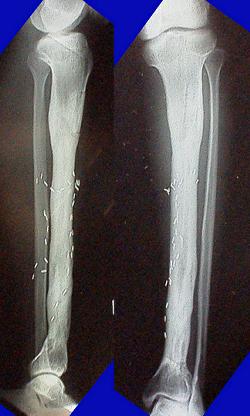

No.05

腫瘍発症

(一年後)

No.06

切除、人工骨移植

(二年後)

No.07

移植後支障なし

No.08

経過観察。

(五年後)

No.09

左変形性膝関節症により高位脛骨骨切り術+内側半月板縫合術

(20年後)